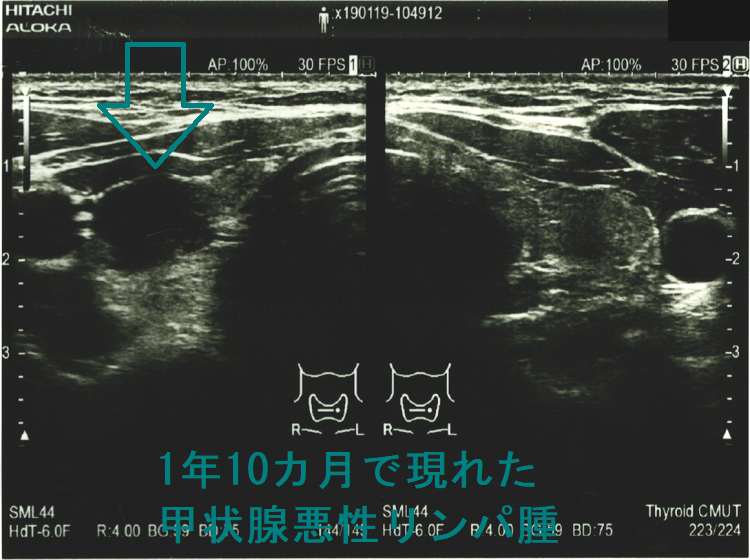

以下は長崎甲状腺クリニック(大阪)にて偶然から見つかった33歳男性の甲状腺悪性リンパ腫(命に係わる甲状腺癌)症例です。早期発見だったため、甲状腺全摘手術で完治し、5年以上経った今も長崎甲状腺クリニック(大阪)に通院されています。

もともと、奥さんの甲状腺機能低下症/橋本病を長崎甲状腺クリニック(大阪)で治療中。「一度、主人も診てやってください」の一言から、特に甲状腺の病気を疑うわけでないのに血液検査と甲状腺超音波エコー検査をおこなったところ甲状腺機能正常橋本病でした。この時(32歳時)は甲状腺悪性リンパ腫を疑う所見はなく、1年後の再診を指示しましたが、来院されたのは1年10か月後。 橋本病は甲状腺癌の発生母体であるため、当然のごとく甲状腺超音波エコー検査を施行。

(写真参照)右葉中部に18.5 x 13.2 x 8.8 mmの甲状腺悪性リンパ腫を認め、大阪市立大学(現、大阪公立大学) 内分泌外科(現在は業務統合のため廃止)にて根治的甲状腺全摘手術をおこない完治。発見が早かったため甲状腺から外に出ておらず、術後の抗がん剤も一切必要なく経過。5年以上経った今も元気に御夫婦で来院されています。もしも、甲状腺超音波エコー検査を行っていなければ、命を失っていた可能性大です。